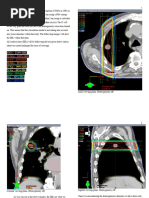

There are also observed differences in the number of monitor units (MUs) needed to deliver the

prescribed dose for each plan, as seen below. The total number of MUs needed for the plan with

no correction applied is 246. Meanwhile, the plan with inhomogeneity correction applied

requires 227MU – less than the plan with no correction. This is a result of the perceived

equivalent path of beams within the plan. Since the plan with no correction applied is calculated

on a water-equivalent homogenous patient, the total amount of electron density across the entire

beam path is much greater than when lung tissue is taken into account, being that the relative

electron density of lung is approximately 0.2-0.3 that of water. Therefore, more monitor units

need to be applied to the plan with no correction applied in order to deliver the same dose to the

same prescription point, as it assumes that there is greater attenuation of the beam over its path,

due to the increased density.

Inhomogeneity correction OFF Inhomogeneity correction ON